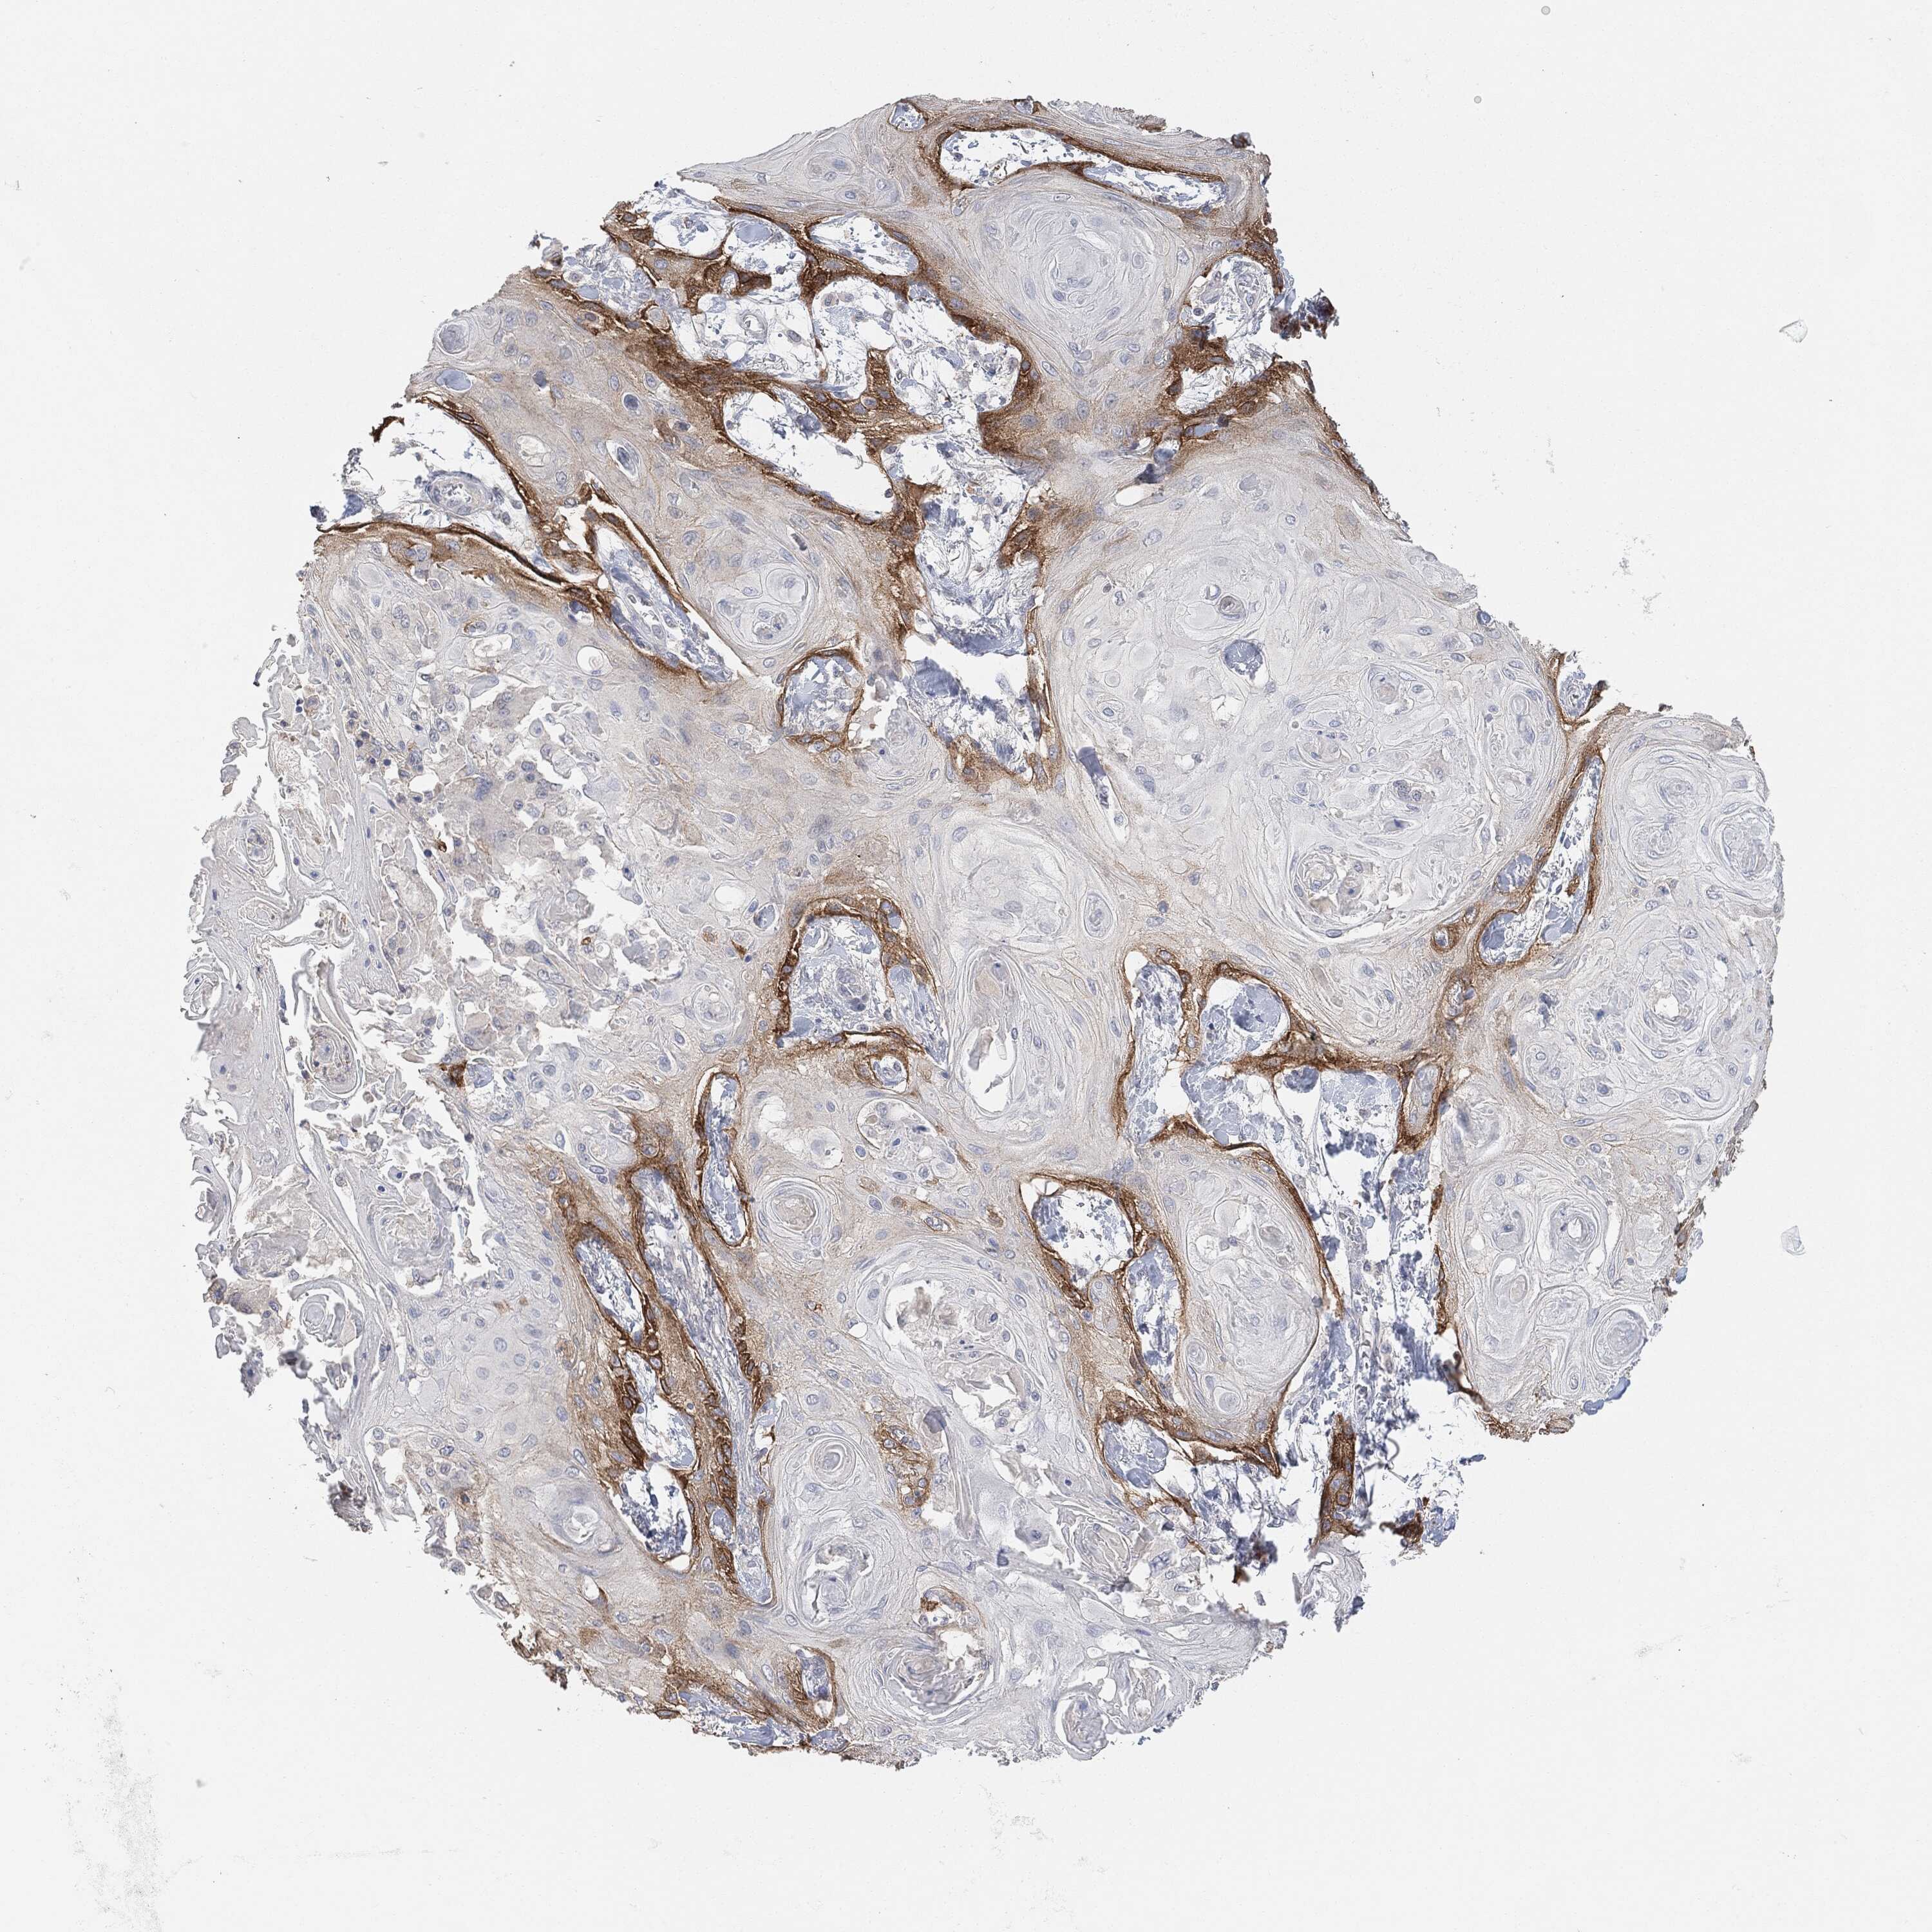

SKIN CANCER - Protein expressioni

A mouse-over function shows sample information and annotation data. Click on an image to view it in a full screen mode. Samples can be filtered based on level of antibody staining by selecting one or several of the following categories: high, medium, low and not detected. The assay and annotation is described here.

Antibody stainingi

Antibody staining in the annotated cell types in the current human tissue is reported as not detected, low, medium, or high, based on conventional immunohistochemistry profiling in selected tissues. This score is based on the combination of the staining intensity and fraction of stained cells.

Each image is clickable and will lead to virtual microscopy that enables deeper exploration of all samples and also displays staining intensity scores, fraction scores and subcellular localization as well as patient and tissue information for each sample.

Basal cell carcinoma